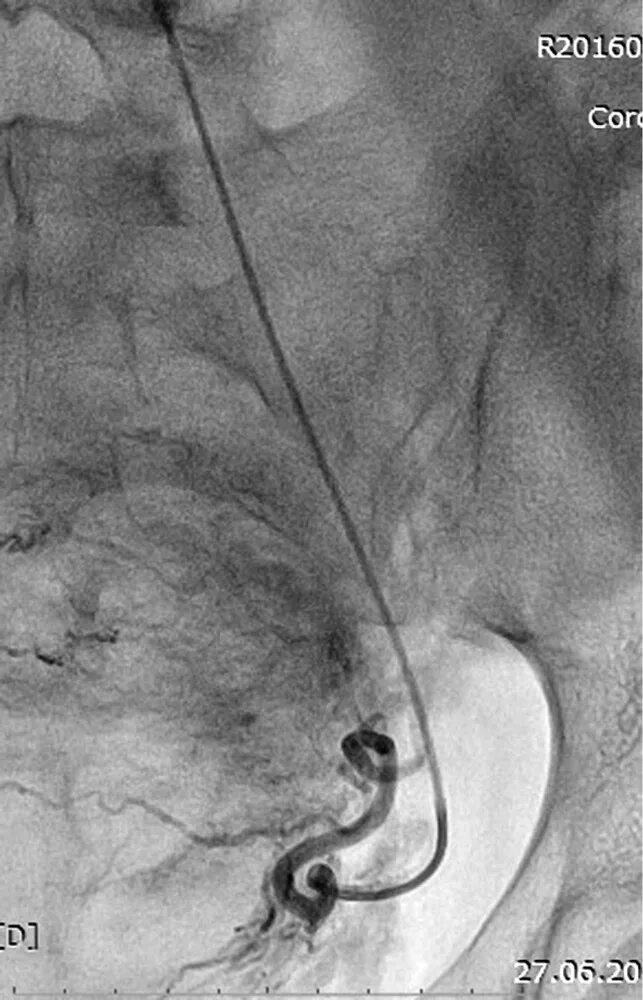

Операция эмболизация маточной артерии